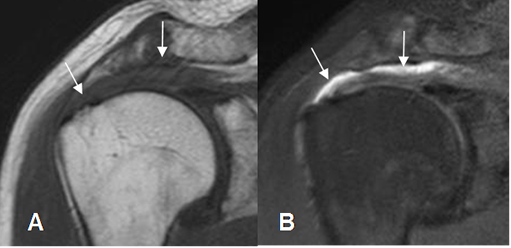

La bursa subacromio-subdeltoidea (SASD) contiene grasa y la presencia de líquido, también indica patología. (Fig 32 y 33).

Fig 32. Bursa SASD normal.

A: RM coronal en T1 y B: RM sagital en T2. Bursa normal, con contenido de grasa. (Flechas delgadas). Músculo deltoides normal. (Flechas gruesas).

C: RM coronal en STIR. Supresión de la grasa, sin encontrar cambios inflamatorios.

Fig 33. Bursa SASD patológica.

A: RM coronal en T1: Pérdida de la grasa normal en la bursa.

B: RM coronal en STIR. Líquido en la bursa SASD, por proceso inflamatorio.